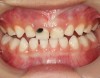

There are several advantages of using SDF in dental treatment. First, it showed an antimicrobial activity against mono-species, dual-species, and multi-species cariogenic biofilm.14-16 Silver ions are bactericidal metal cations that inhibit biofilm formation.17 Studies have indicated that silver interacts with sulfhydryl groups of proteins and DNA, thus altering hydrogen bonding and inhibiting respiratory processes, DNA unwinding, cell-wall synthesis, and cell division.18 At the macro level, these interactions affect bacterial killing and inhibit biofilm formation.17 Second, fluoride promotes caries lesion remineralization. Fluoride has been indicated to react with hydroxyapatite and generate calcium fluoride, which is a reservoir of fluoride, and facilitate further remineralization.19 An ex vivo study reported surface microhardness of the surface layer of the arrested caries after SDF applications was comparable with the unaffected sound dentin20 (Figure 1 and Figure 2). This is consistent with another study, in which a high remineralized zone was observed on the surface of arrested caries from exfoliated teeth with SDF treatment21 (Figure 3 and Figure 4). Third, its application procedures are simple and do not require injection or drilling, and the treatment does not involve expensive support infrastructure equipment such as piped water and electricity. The simplicity of the treatment is conducive to treating caries in apprehensive young children who may have intense dental fear, uncooperative patients with special needs, or elderly patients who have difficulty adapting to traditional dental care. It also allows trained workers to deliver the treatment to people who live in the area but who may not be able to easily access dental service.22 Patient compliance and satisfaction is often good when the patient is provided a clear explanation of the treatment outcome.23,24 Finally, the cost of SDF treatment is low and should be affordable in most communities.

Fig 3. Scanning electron microscope (SEM) images of the dentin carious lesions: surface morphology of arrested carious lesion. (image from Mei, et al, 2014, ref 21 [reprinted with approval])

Figure 3